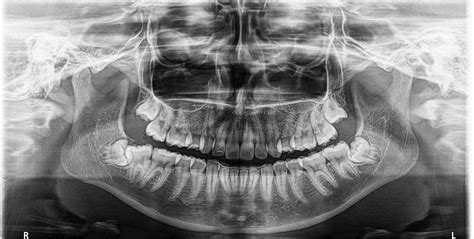

Resultados Radiográficos

En la ortopantomografía observamos un adecuado paralelismo radicular con gérmenes de cordales en formación y con suficiente espacio habitable. También observamos imágenes radiolúcidas de caries oclusales en molares inferiores. La telerradiografía lateral de cráneo muestra una normoclusión con perfil armónico (figs. 15 y 16).

Figura 16. Telerradiografía lateral de cráneo postratamiento.